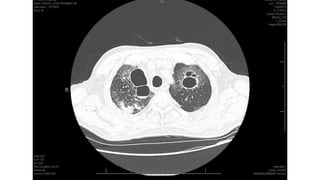

Miliary pattern

Intersticial Randomic micronodular distribution